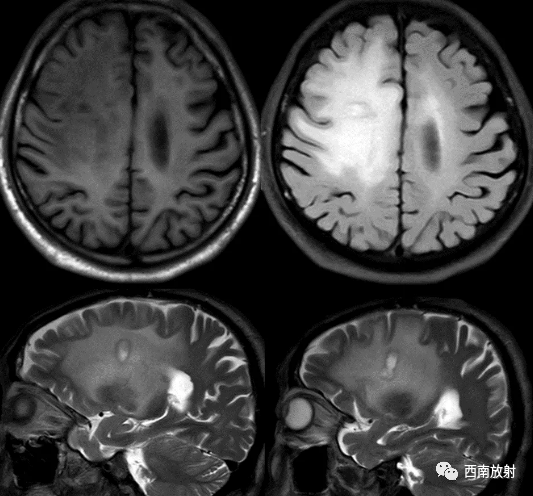

中枢神经系统淋巴瘤主要发生在脑内深部白质,病灶大多位于幕上。多数病灶邻近脑室。病灶形态多为团块状,较典型表现如同“握拳”者。位于胼胝体压部的病灶沿纤维构形,形似蝴蝶,颇具特征。该病“瘤周水肿”在T2WI呈高信号,不仅反映该部位脑组织水分增加,还有肿瘤细胞沿血管周围间隙浸润、播散的因素;另一特征为“瘤周水肿”与肿瘤体积不一致。本病大多数肿瘤体积相对较大,具有较明显占位效应,但周边水肿相对轻微。非免疫功能低下者发生淋巴瘤时,瘤体内囊变、坏死少见。本病也可发生在中枢神经系统的其他部位,脑外受累部位有颅骨、颅底、脊髓等。

▲病例:脑淋巴瘤。脑深部结节病灶,具有刀切征、凹陷征或肚脐凹征、尖角、多发。DWI呈稍高信号,形态上怪异,波普NAA及Cho减低,出现导致LL峰。颈部、胸廓入口区及腋窝多发淋巴结肿大并相互融合。